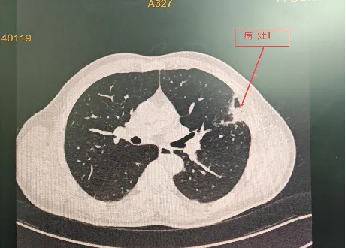

程大叔的胸部CT

程大叔的女儿立即将他带到自贡市第四人民医院呼吸与危重症医学科,接诊的医生阅读胸部CT检查单后并分析,考虑良性的炎性病灶可能性更大,以最快的速度安排了肺穿刺活检